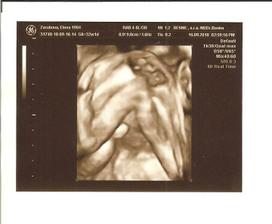

27.6. nedela - 3D ultrazvuk v HC, vsetko je ok, potvrdeny chlapec, nadherny zazitok

16.9. stvrtok - 4D ultrazvuk - Banovce nad Bebravou, MUDr. Baskova - vsetko ok, potvrdeny na 300% chlapec, 32tt+1 ale podla utz 32+5, vaha je cca 2000g, mame cca 30cm po kostrc, co by malo byt s nozickami asi 44cm